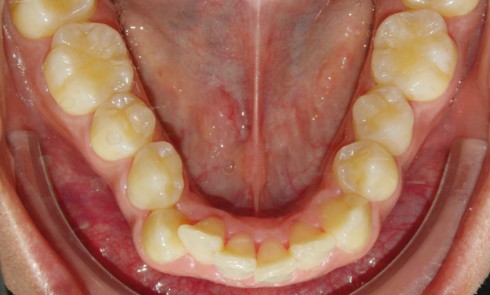

Présentation du cas Il s’agit d’un patient adulte de 28 ans (fig. 1) présentant une classe I, une dysharmonie dento-maxillaire (DDM),...